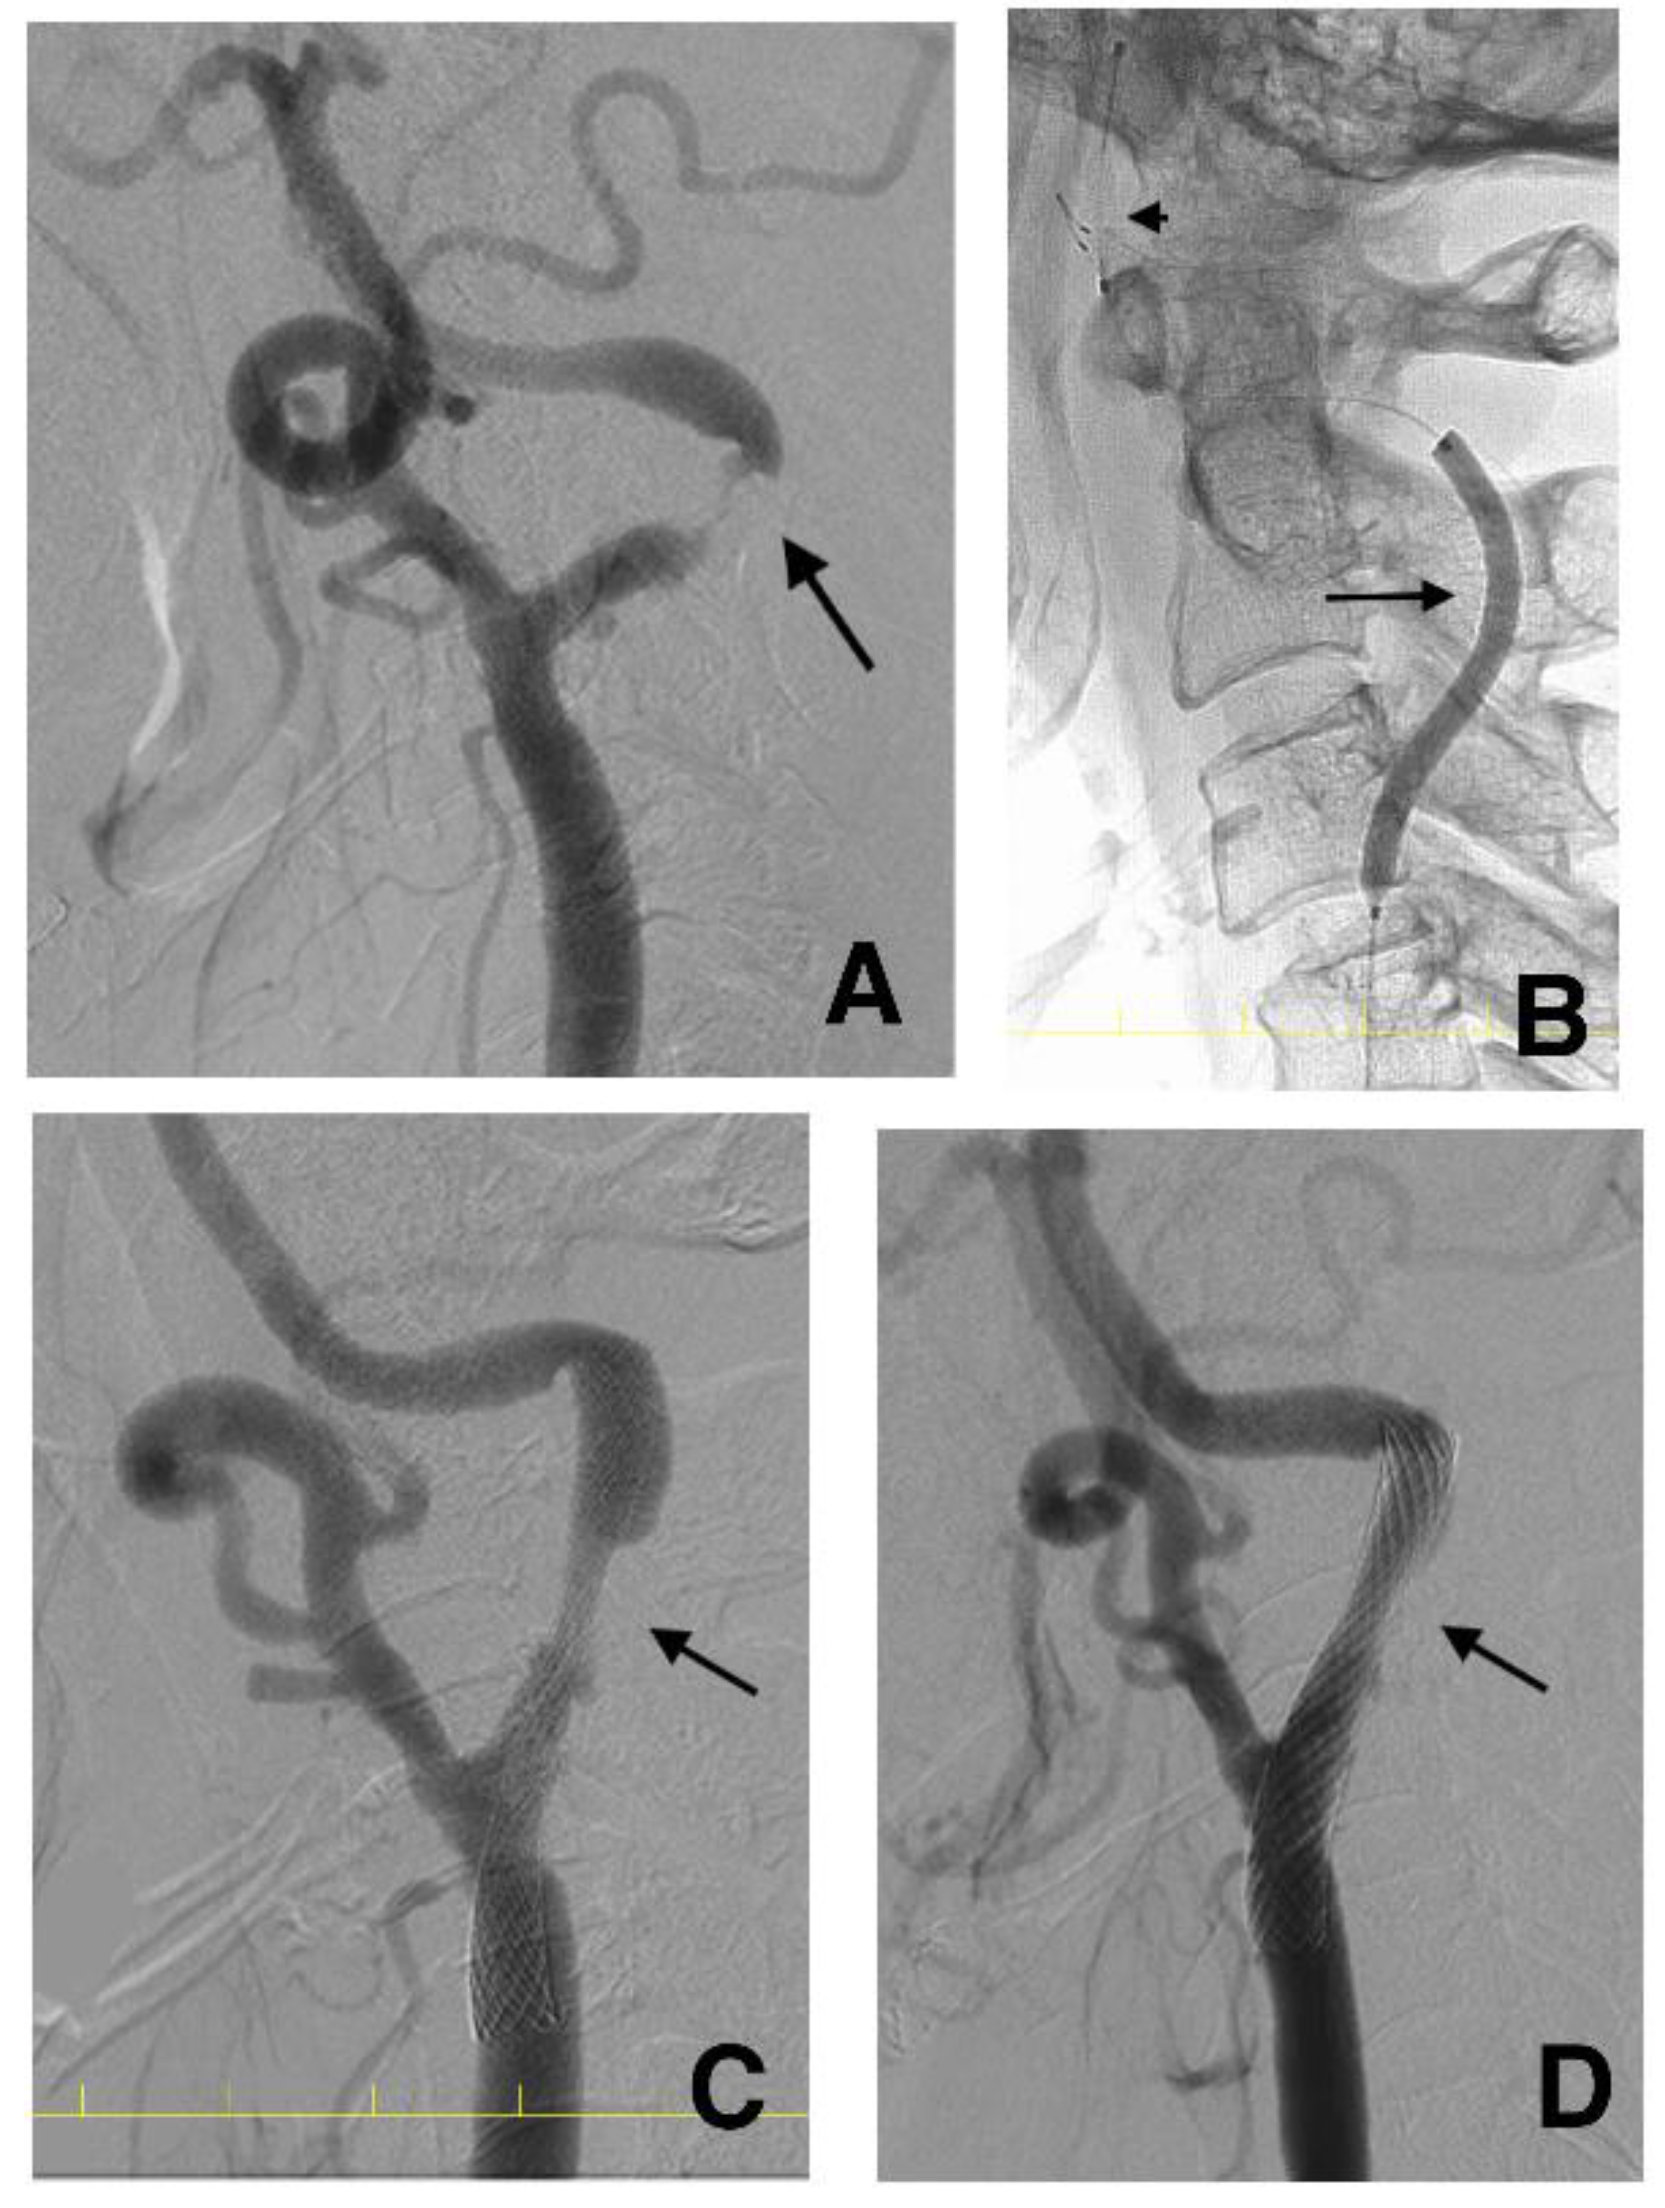

Patients with IPH (IPH group) underwent gradual-expansion CAS. For pre-SA, we used a balloon catheter 3.0 mm in diameter for lesions with MLD < 2.0 and inflated the balloon to 3.0 mm or a semi-compliant balloon catheter 4.0 mm in diameter for lesions with MLD ≥ 2.0 mm and inflated the balloon to 4.0 mm. We did not overinflate them. Subsequently, a closed-cell stent was deployed (Figure 3).

Figure 3.

Serial angiograms before (A), immediately after (C), and at four months after (D) carotid artery stenting (CAS) and the balloon (arrow) and filter (arrowhead) during inflation (B) in the same case as in Figure 2. The minimal luminal diameter is 0.26 mm (A: arrow). The semi-compliant balloon flexibly dilates the lesion along the artery (B: arrow). The minimal stent diameter is 2.69 mm after CAS (C: arrow), and the minimal stent diameter at four months is 3.97 mm (D: arrow). CAS, carotid artery stenting.

Patients without IPH (non-IPH group) underwent standard CAS in our institution. A balloon catheter 4.0 mm in diameter for pre-SA was used and overinflated up to 4.23 mm. However, in patients with an ex-CS, the 4.0 mm balloon for pre-SA was not overinflated to prevent hyperperfusion syndrome [11]. Subsequently, a closed-cell stent was deployed (Supplementary Table S1).